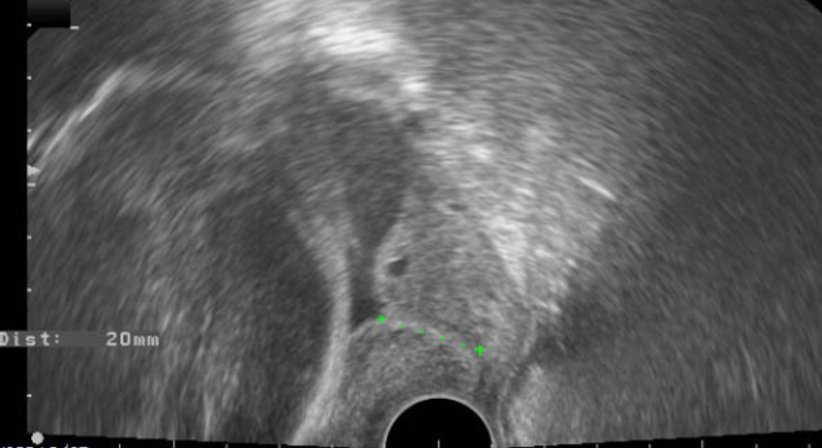

Besonders ist auf die Wichtigkeit der Anamneseerhebung im Rahmen der Erstuntersuchung hinzuweisen. Der wichtigste prädiktive (vorhersagende) Parameter für eine Risikoschwangerschaft hinsichtlich Frühgeburt ist eine bereits stattgefundene Frühgeburt in einer vorhergehenden Schwangerschaft!! In diesem Fall sind engmaschige Kontrollen im Rahmen der Schwangerenbetreuung mit sonographischer Gebärmutterhalsvermessung sowie Vaginalabstrichen zur Infektionsdiagnostik durchzuführen.